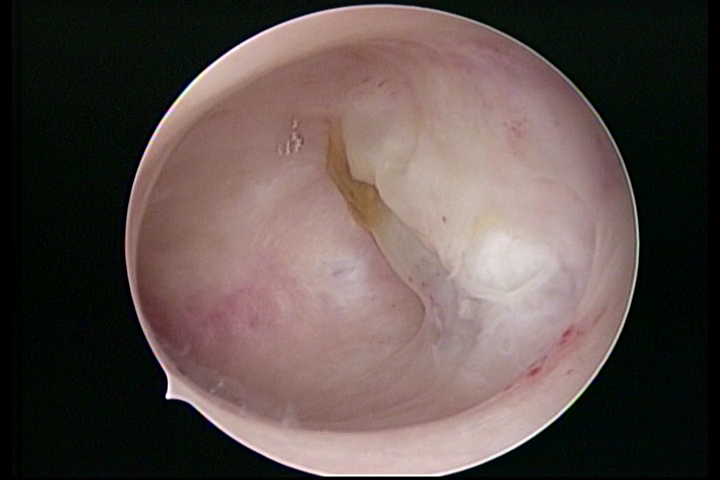

Sinéquia TIPO FIBROSA

• SINÉQUIA TIPO FIBROSA